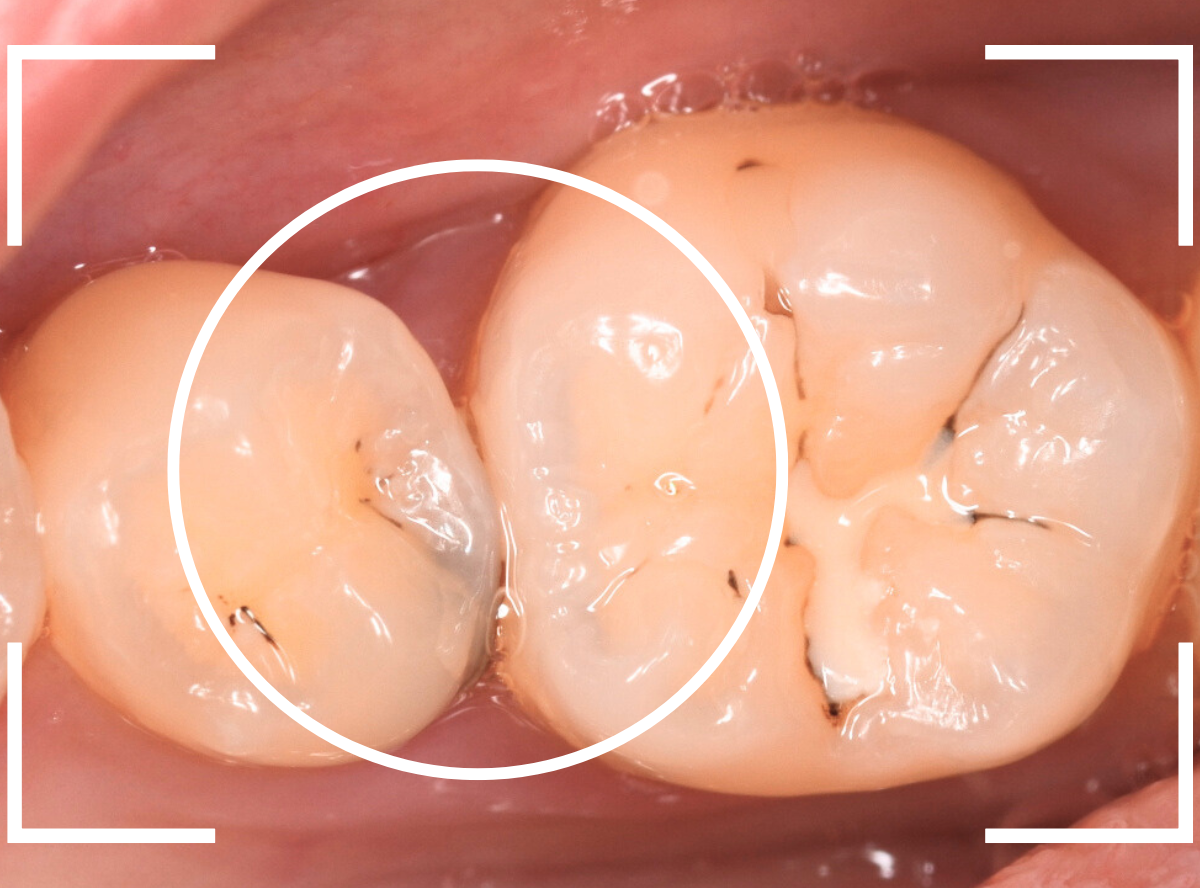

Case.28 虫歯治療後、半年以上来院されなかった患者さん

虫歯を治療して、セメントで歯を削った部分を封鎖した後、再修復を検討中で、半年以上来院されなかった患者さんです。

虫歯を治療して、セメントで封鎖した状態というのは、家でいえば、しっかりした屋根がない状態です。

今回は、セメントの一部がはがれる程度で済んでいましたが、虫歯が再発し、再治療、最終修復物の変更の可能性も出てきます。

皆さんも治療は中断せずに最後まで通院するようにしてくださいね。